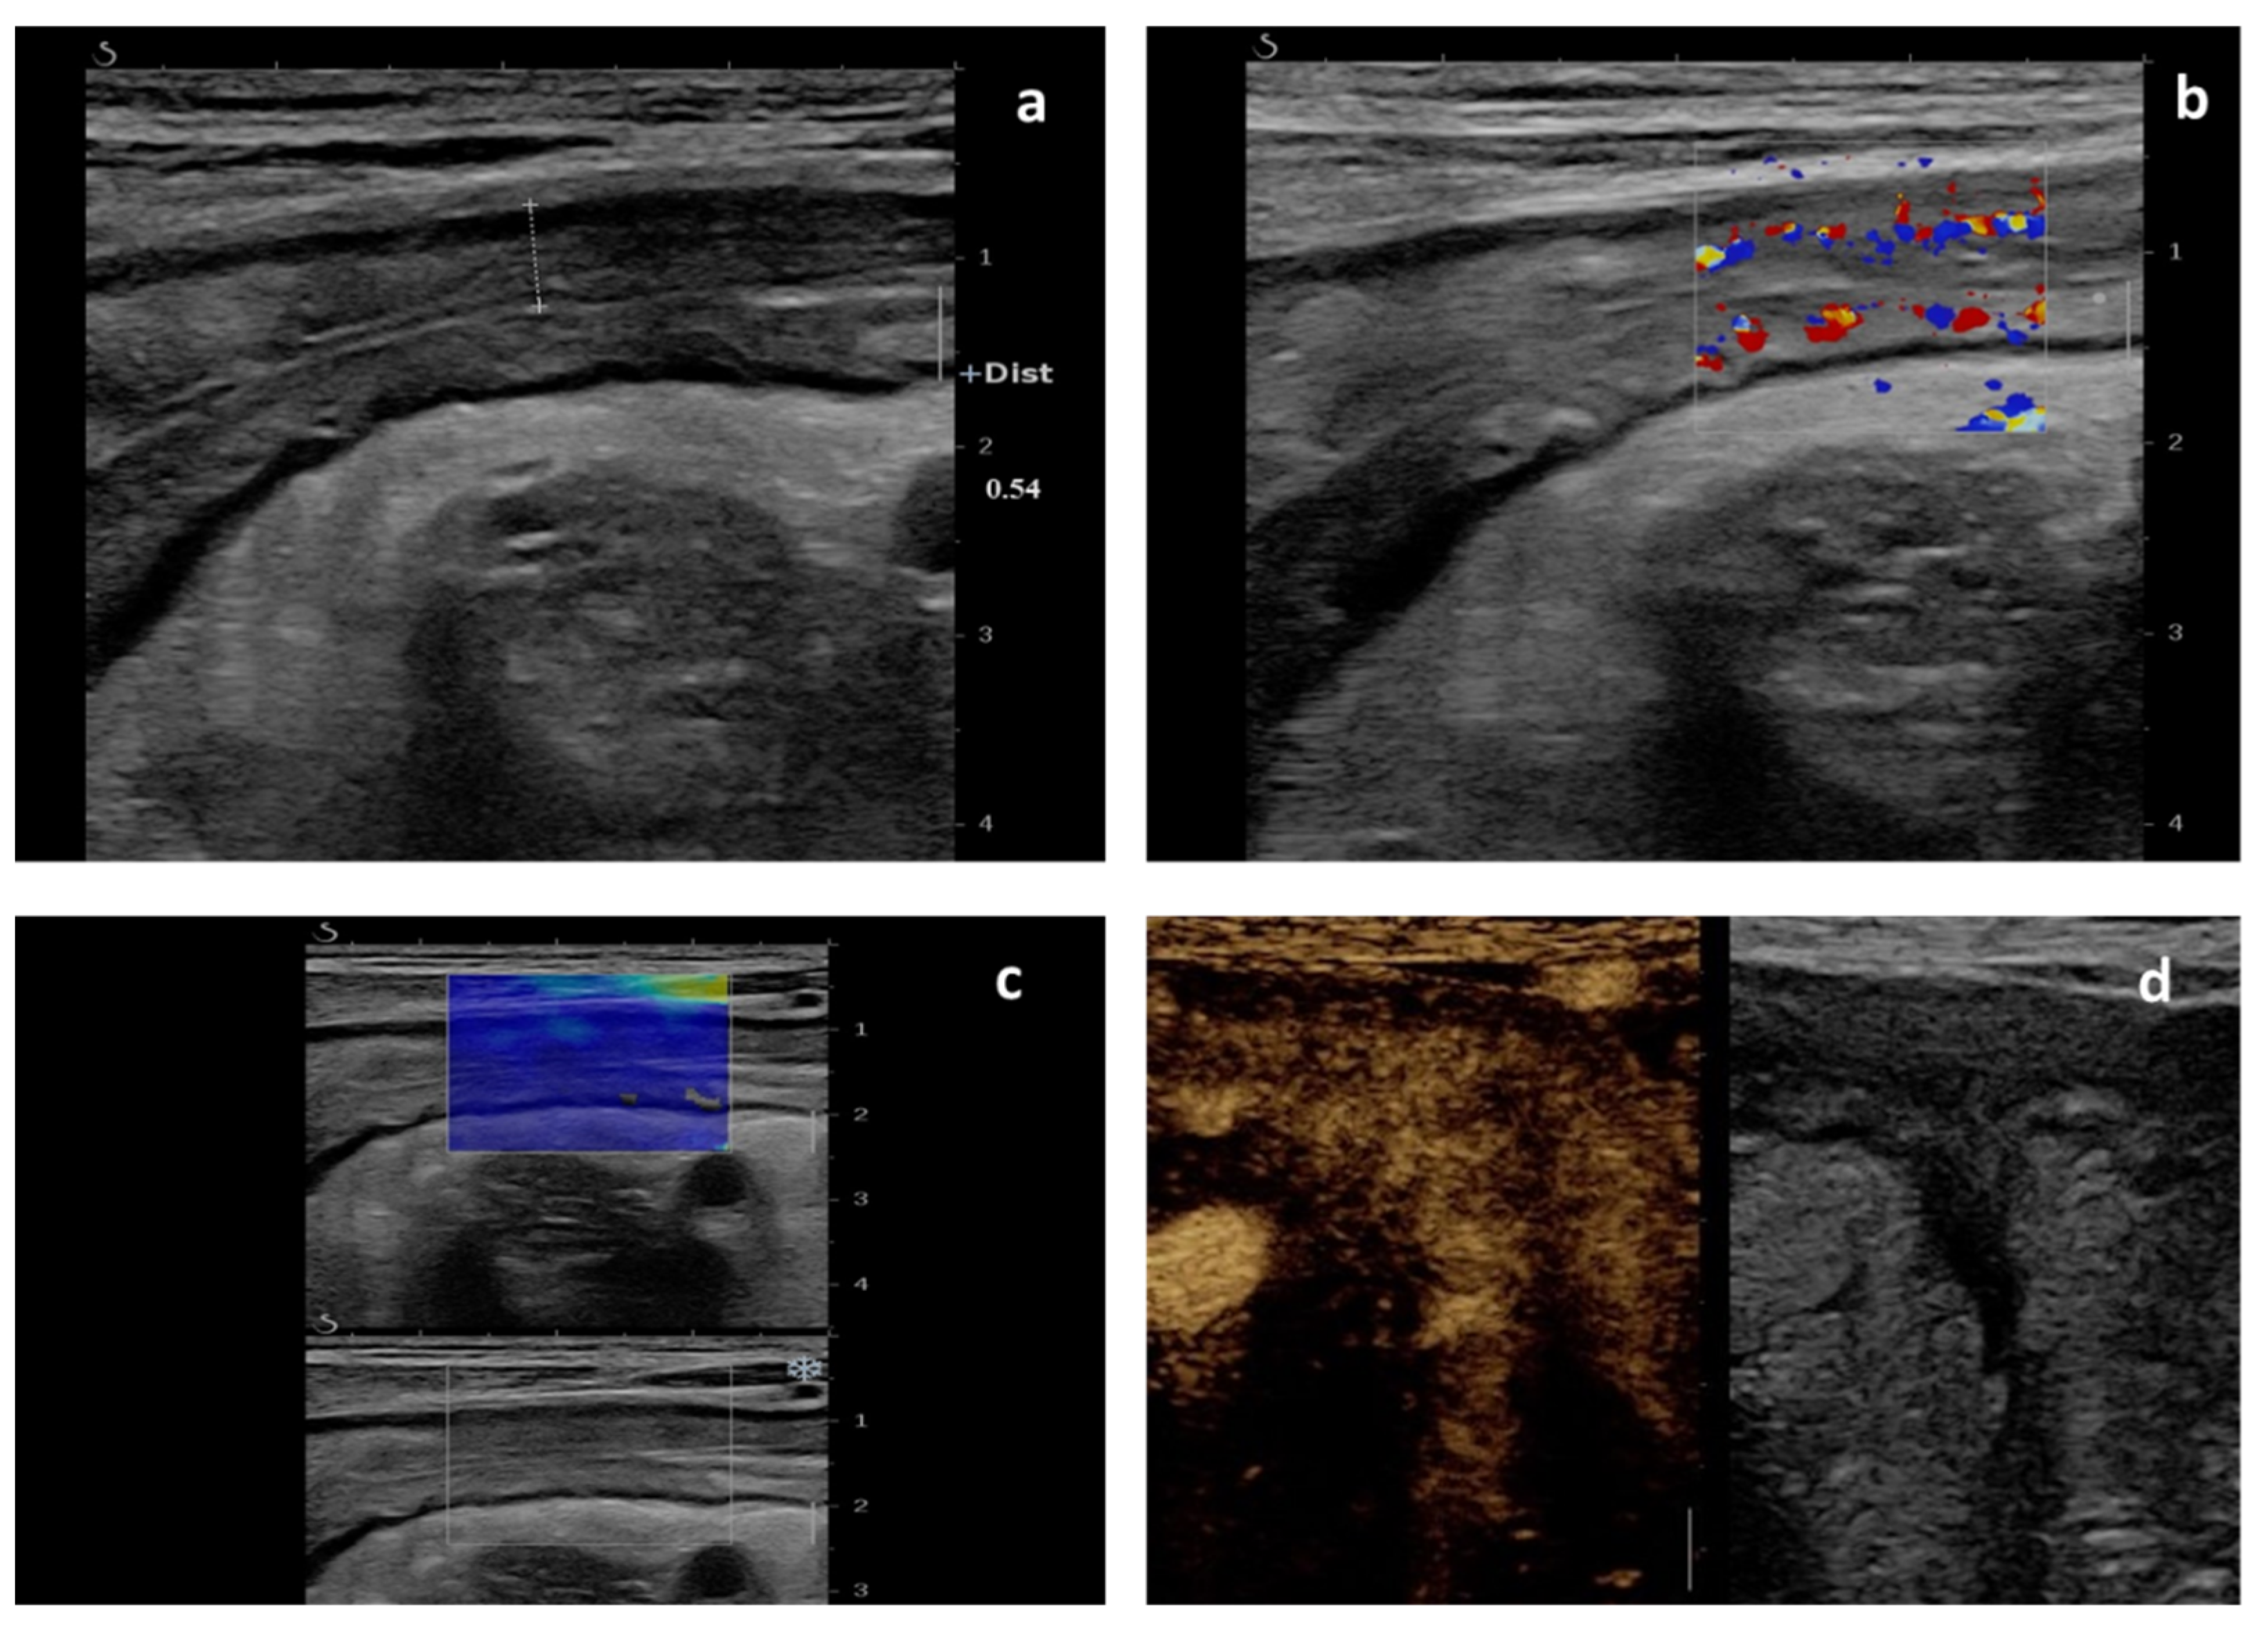

2. Standard Intestinal Ultrasound and Color Doppler

3. Small Intestine Contrast-Enhanced Ultrasonography (SICUS)

4. Contrast-Enhanced Ultrasonography (CEUS)

5. Elastography